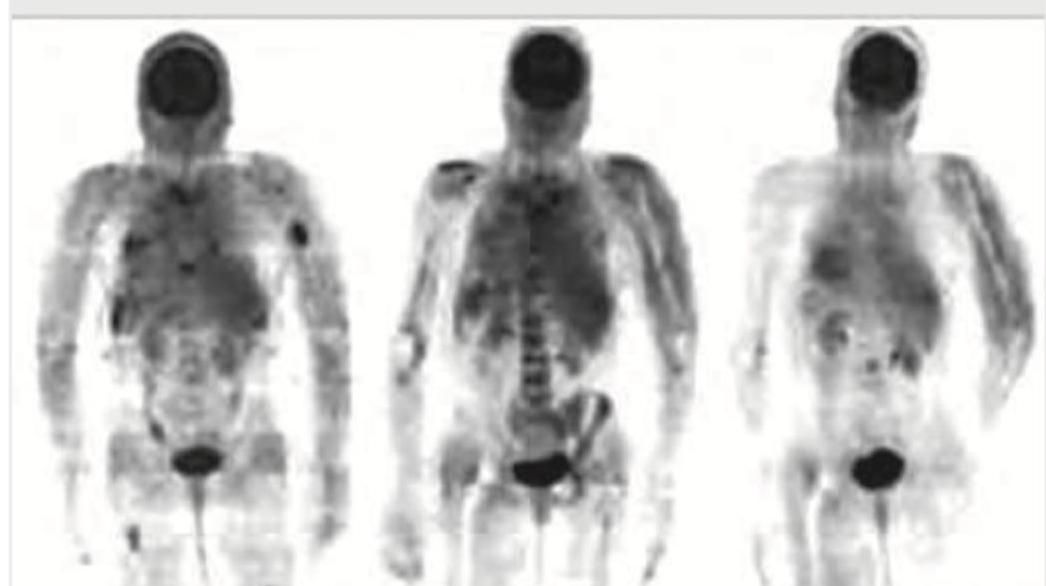

Explanation: ***PET scan*** - The image displays a **whole-body imaging technique** with areas of increased **radiotracer uptake**, characteristic of **PET-CT (positron emission tomography) scans** using **FDG (fluorodeoxyglucose)**. - **FDG-PET-CT** is the **gold standard** for **staging and monitoring treatment response** in lymphomas, including NHL treated with RCHOP regimen. - It detects areas of **high metabolic activity** typical of viable tumor cells, and response is assessed using **Deauville criteria** or **Lugano classification**. - Post-treatment PET-CT helps differentiate between **residual viable tumor** and **fibrotic tissue**, which is crucial for management decisions. *HIDA scan* - A HIDA (hepatobiliary iminodiacetic acid) scan primarily evaluates the **hepatobiliary system** (gallbladder and bile ducts) for conditions like **acute cholecystitis** or bile duct obstruction. - It uses Tc-99m labeled radiopharmaceutical and does not produce a whole-body image with generalized metabolic uptake as shown. *MUGA scan* - A MUGA (multi-gated acquisition) scan is used to assess **cardiac function**, specifically the **left ventricular ejection fraction (LVEF)**. - It's often performed **before and during anthracycline therapy** (like doxorubicin in RCHOP) to monitor for cardiotoxicity. - It focuses on the heart and does not provide a whole-body metabolic assessment for tumor response. *Bone scintigraphy* - **Bone scintigraphy** (bone scan) uses Tc-99m MDP to visualize **bone metabolism** and detect fractures, infections, or skeletal metastases. - While it uses a radiotracer, the uptake pattern is limited to the skeletal system and shows **osteoblastic activity**, unlike PET-CT which shows soft tissue and nodal metabolic activity throughout the body.

Explanation: ***Gadolinium*** - The image shown is a **PET scan**, which utilizes radiotracers that emit positrons, typically labeled with isotopes like 18F, 11C, 15O, or 13N. - **Gadolinium** is used as a contrast agent in **Magnetic Resonance Imaging (MRI)**, enhancing signal intensity by shortening T1 relaxation times, which is a different imaging modality. *18 Fluoride* - **18 Fluoride (18F-FDG)** is the most commonly used radiotracer in PET scans. - It is a glucose analog that accumulates in metabolically active cells, such as cancer cells, making it useful for **oncologic imaging**. *FLT* - **FLT (3'-deoxy-3'-[18F]fluorothymidine)** is another PET radiotracer. - It measures **cellular proliferation** by reflecting DNA synthesis, making it useful for assessing tumor growth rate. *FMISO* - **FMISO ([18F]fluoromisonidazole)** is a PET radiotracer used to detect **hypoxia** (low oxygen levels) in tissues. - It is often used in oncology to identify hypoxic regions within tumors, which can be resistant to radiation therapy.